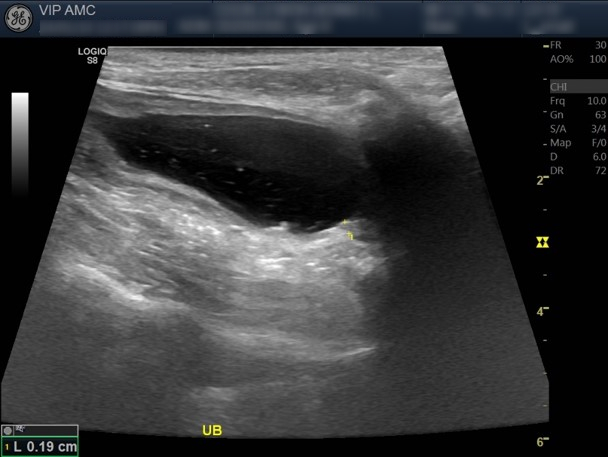

방광목 부분의 융기 된 병변을 볼 수 있습니다. 수술 후 항암제 투약 전까지 더 비후된 것 확인됐습니다.

* 항암치료 지속하며 융기됐던 곳이 점점 완화되는 것을 볼 수 있습니다.

* 항암치료를 지속하며 융기됐던 곳이 점점 완화되었고 정상 범위에서 유지 중입니다.